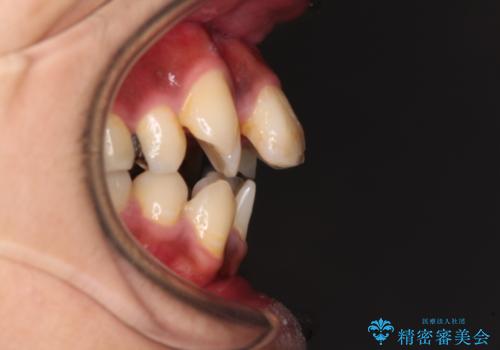

八重歯と開咬 ワイヤー装置での抜歯矯正

- 前歯のデコボコと八重歯、開咬を気にして来院された患者様です。

骨格的に下顎骨が上顎骨に対して後退位であったため、上顎の左右第一小臼歯を抜歯し、デコボコを改善するとともに開咬を改善していくこととしました。